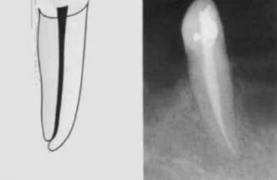

Type 1

Single canal from pulp chamber to apex

1